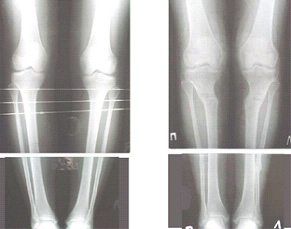

Картинки - в приложении.Будут вопросы - готов ответить.

Ещё картинка - схема. Хотя у Соломина всё написано.

Вот ещё картинки, которые отправлял в Ортопод. Коррекция кривизны и удлинение на 3 см.